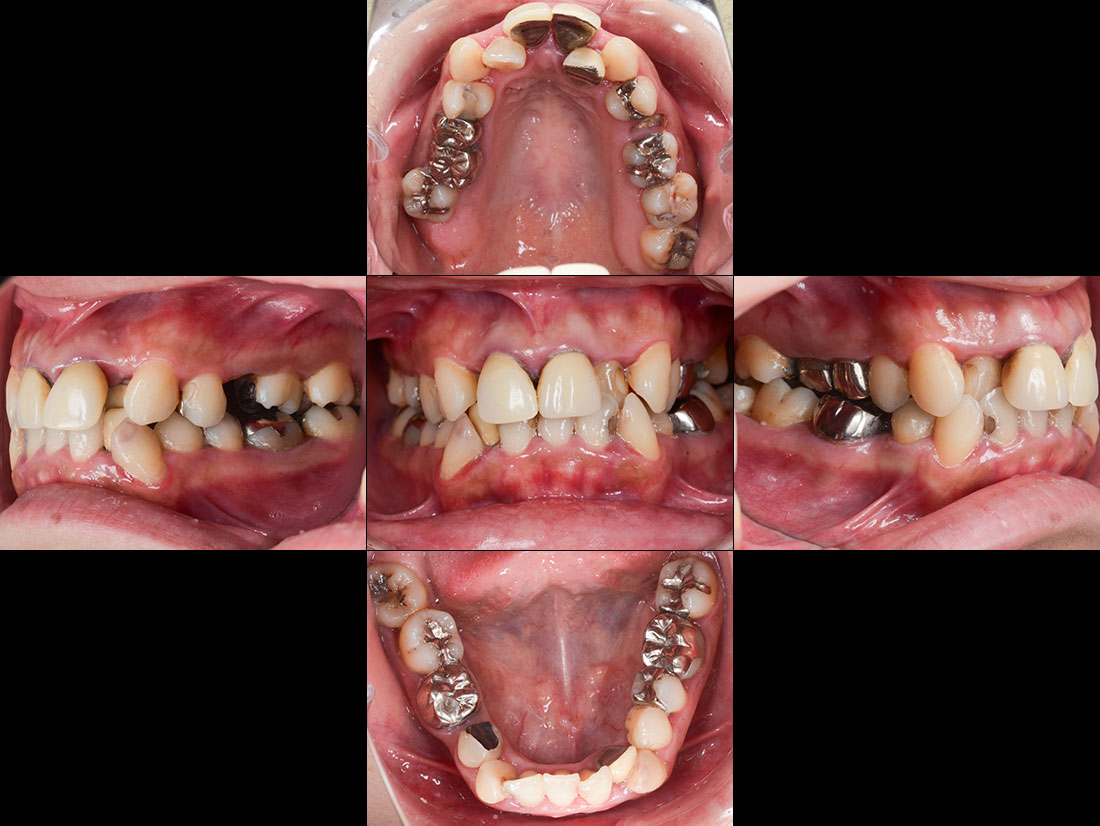

ご相談内容

- 歯並びが気になる

- 矯正をする時間が取れないので被せ物で治していきたい

治療前

今回は前歯をグラデーションカラーのジルコニア、奥歯をセレックで治療しました。

見た目の美しさのポイントになるスマイルラインも整っています。